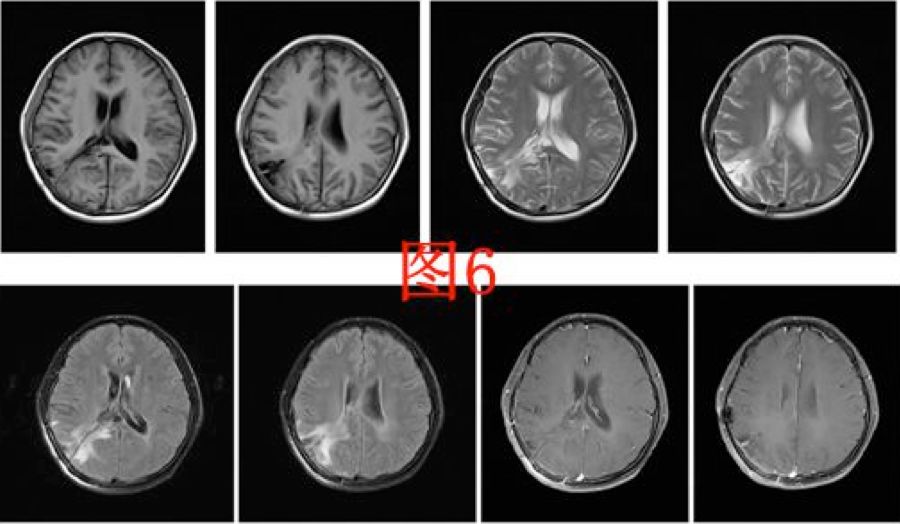

患者于术后第64天再次入院,入院后行头部MRI(图4)检查提示右侧侧脑室颞角、后角扩张并周围脑组织水肿、中线明显移位,并行腰穿测压为280cmH2O,诊断为右侧侧脑室三角区脑膜瘤切除术后孤立颞角综合征,遂于术后第68天行侧脑室颞角腹腔分流术,分流管为美敦力可调压力分流管,术中设定压力范围为105~125mmH2O,术后复查头部CT以及MRI(图5、6)。

图6.显示V-P分流术后复查头部MRI。

孤立颞角综合征(entrapped temporal hornsyndrome)在1947年由CAIRNS等首次报道[2],目前文献报道少[1, 3-7]。侧脑室三角区是颞角的流出道,解剖位置相对狭窄[8]。当因肿瘤、出血、感染等疾病导致三角区梗阻时,颞角的脉络丛仍持续分泌脑脊液,局部脑脊液积聚,引起颞角扩张,影像学上表现为侧脑室三角区呈气球样膨胀,周围的间质水肿明显,呈“日环征”[2]。本病例图7箭头所指。本病例考虑为手术切除肿瘤后侧脑室三角区少量出血后粘连,并局部脑室外引流管过度引流后导致三角区封闭后引起。

图7. 磁共振表现为侧脑室三角区呈气球样膨胀,周围的间质水肿呈“日环征”